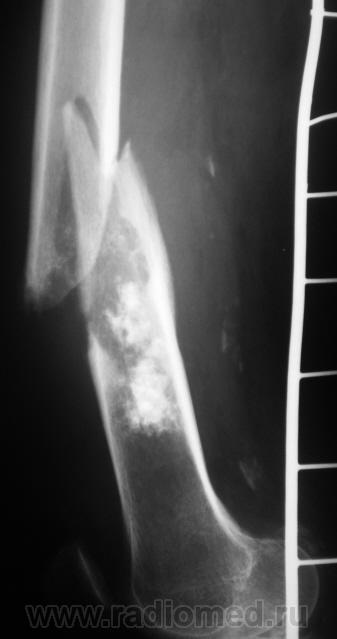

Ну, и, после "репозиции".

н\3 бедра со смещением по длине и ширине. Отломки находятся под углом открытым кпереди прим. в 10-15 град.

После репозиции дистальный отломок смещён латерально на ширину кортикального слоя.

А не создается-ли впечатления, что представленный перелом патологический? Первый снимок произведен через час после травмы.

костных структур в проекции прелома, то действительно это патологический перелом. Честно не сразу обратил внимание.

Что это - не скажу (под рукой нет литературы). Но. 1.Процесс опухолевый - в средней части, по заднему контуру отмечается вздутие кости. 2.Относительно длительно текущий - вздутие достаточно протяженное. 3.Пока еще относительно доброкачественный - кортикальный слой созранен. 4. Многоузловой (мультифокальный) - не менее 3-х узлов/фокусов. В зависимости от возраста/пола/анамнеза вполне может быть метастатическим. 5.Перелом все-таки патологический - линия перелома проходит через верхнюю часть патологического субстрата.

Это может оказаться и безобидным обызвествлением костного мозга после инфаркта, хондромой или хондросаркомой. - Уроки Татьяны Валентиновны. Но вздутия не вижу - его в боковой проекции симулирует третий фрагмент в месте перелома. Ну а метастаз - маловероятен... Опять же - "горим" на сочетанной патологии...

Как по мне, так там наоборот, локальное (хотя и на достаточном протяжении) УТОЛЩЕНИЕ кортикального слоя по задней поверхности, хотя и в сочетании с умеренным вздутием.

Данная рентген-картина может быть характерна и для хондросаркомы.

Вот, и у меня зародилась такая подлая мысль о наличии "хондро", и даже очень вероятно хондросаркомы.

хочу поддержать доктора Анатолия Шумакова: перелом вряд ли патологический, обызвествление костного мозга бедренной кости и вероятно стенок сосудов